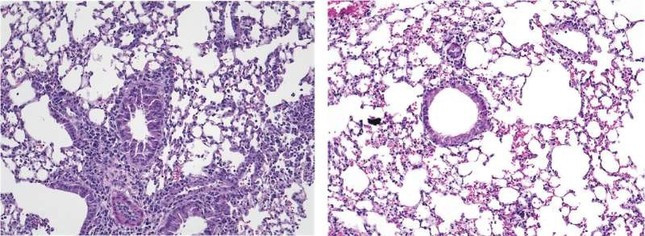

| Kích hoạt ILC2 gây viêm ở phổi chuột (ảnh trái), nhưng tình trạng này giảm đi khi điều trị bằng Yoda1 để kích thích các kênh Piezo1 (ảnh phải). |

Nhóm của Akbari phát hiện ra rằng, khi không có Piezo1, ILC2 của chuột trở nên hoạt động mạnh hơn bình thường để phản ứng với các tín hiệu gây dị ứng và các con vật này bị viêm đường hô hấp gia tăng. Ngược lại, điều trị bằng thuốc có tên Yoda1 kích hoạt các kênh Piezo1 làm giảm hoạt động của ILC2, giảm viêm đường thở và giảm bớt các triệu chứng tiếp xúc với chất gây dị ứng.